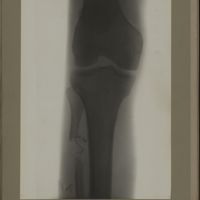

0181 - Page 69 - [Radiographies du genou]0181 - Page 69 - [Radiographies du genou]

0188 - Page 76 - [Radiographie du genou]0188 - Page 76 - [Radiographie du genou]